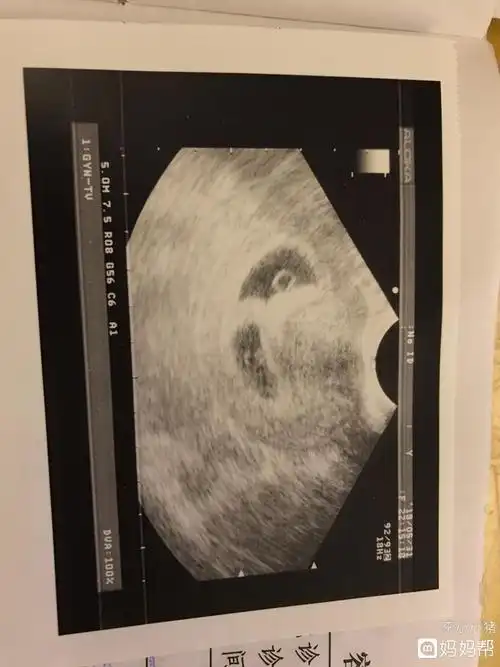

宝宝有胎心胎芽了

接健康胎心胎芽喽